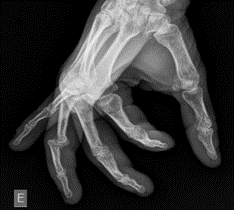

Image 1: Lateral X-ray of the left fourth digit demonstrating a dorsal dislocation at the PIP joint. Case courtesy of Leonardo Lustosa, Radiopaedia.org, rID: 99559

Finger dislocations are common in contact sports, with PIP dislocations being one of the most common dislocations associated with sports injuries.2 Dislocations of the DIP and PIP joints can be in the dorsal, volar, and lateral directions, with dorsal dislocations being the most common.

Volar plate injuries, including avulsion or oblique fractures into the PIP joint, are commonly seen with dorsal PIP dislocations. This injury warrants careful consideration in any patient with a history of a hyperextension mechanism injury to any digit. This will often be reported as having a “jammed” finger when playing contact sports or attempting to catch/corral a ball.3 Volar plate fractures involving greater than 30% of the articular surface may no longer be stable and may require surgical fixation. These warrant timely follow-up with hand surgery.3,4 If left untreated, dorsal dislocations and volar plate injuries can result in a persistent swan neck deformity. Irreducible dorsal dislocations, while rare, should prompt concern for an interposed volar plate. These require prompt orthopedic consultation for open reduction.5 Central slip extensor tendon injuries can be seen with volar PIP dislocations and can result in a Boutonniere deformity if missed or left untreated.4